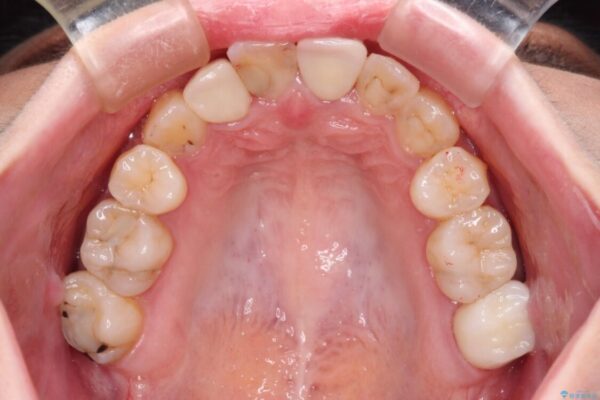

治療前

• 虫歯治療ついでに歯並びの後戻りを改善 インビザラインによる矯正治療 治療前画像